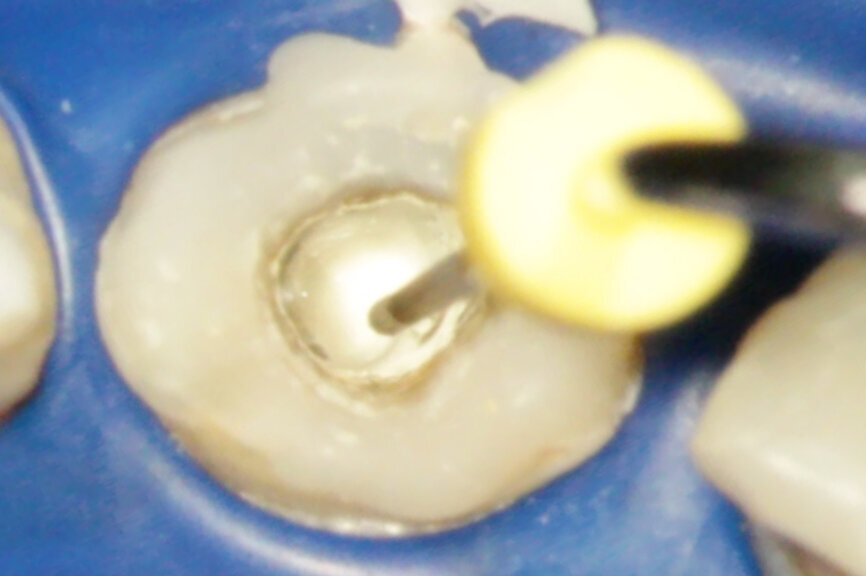

Vital pulp therapy has become more popular in recent years. Calcium hydroxide has been the most common material for pulp capping, but MTA has shown even better results in biocompatibility and outcome.[3] Cases with large carious pulp exposure can be treated successfully with partial pulpotomy and MTA as a capping agent, keeping teeth vital (Figs. 1a–e).

Fig. 1a: (a) Deep carious lesion. (b) Partial pulpotomy. (c) MTA application with the MAP System and PD MTA White. (d) Filling. (e) Post-op radiograph showing the pulp capping with MTA.

Fig. 1b: (a) Deep carious lesion. (b) Partial pulpotomy. (c) MTA application with the MAP System and PD MTA White. (d) Filling. (e) Post-op radiograph showing the pulp capping with MTA.

Fig. 1c: (a) Deep carious lesion. (b) Partial pulpotomy. (c) MTA application with the MAP System and PD MTA White. (d) Filling. (e) Post-op radiograph showing the pulp capping with MTA.

Fig. 1d: (a) Deep carious lesion. (b) Partial pulpotomy. (c) MTA application with the MAP System and PD MTA White. (d) Filling. (e) Post-op radiograph showing the pulp capping with MTA.

Fig. 1e: (a) Deep carious lesion. (b) Partial pulpotomy. (c) MTA application with the MAP System and PD MTA White. (d) Filling. (e) Post-op radiograph showing the pulp capping with MTA.